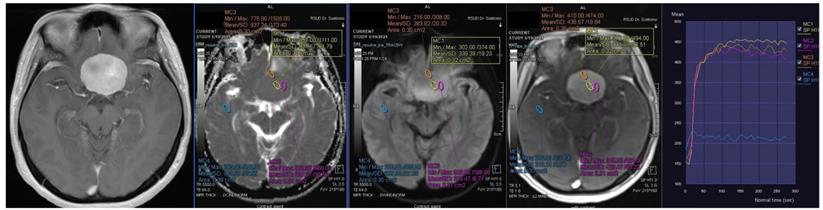

Figure 2

Contrast-enhanced T1-weighted imaging, diffusion weighted imaging, and dynamic contrast enhancement magnetic resonance imaging in a 49-year-old man with histopathologically confirmed World Health Organization grade II atypical meningioma. The mean apparent diffusion coefficient value was 0.871 x10-3mm2s-1. The time-signal intensity curve showed rapid initial enhancement followed by the washout phase (Type IV).

Int J Med Sci Image